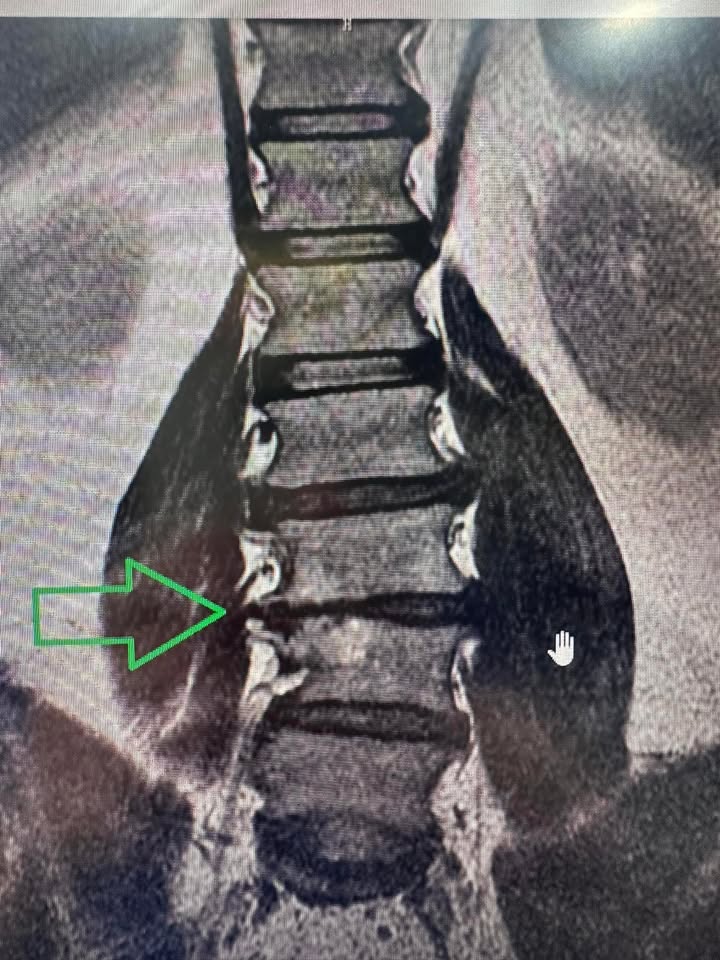

超嚴重的滑脫合併椎管狹窄走路無法超過5分鐘

☑️這個就是我們台語講的龍骨「走山」

🟢說實在的這個患者真的不好處理,年紀也70多歲了,因為他來診所的時候整支腳特別是左腳都沒力,早期都是拿拐杖🩼來門診,所有的護士都可以作證,真的很辛苦的治療將近兩個多月狀況才慢慢改善到最後甚至可以不用拐杖在公園走好幾圈,這中間連我差一點都要放棄,請他去大醫院開刀,因為治療的一開始效果很慢,幾乎治療的前面一個月效果很慢,所以連我也很著急,結果一直到治療第九次以後開始明顯改善⋯⋯⋯

🔵 🌐 治療思維:按照骨科思維,腰椎滑脫的患者就是要固定!除非患者的核心肌群被建立起來,我們使用減壓的方法讓患者的神經根位移,先讓疼痛症狀改善,在教育患者如何建立核心肌群,古典針灸在增強肌力這方面也有幫助,林阿伯一開始的棒式運動只有撐不到10秒,在經過六週的治療後,可以撐到90秒!想當然核心肌群穩定他老人家的韌帶跟肌肉,整個症狀幾乎完全消失!